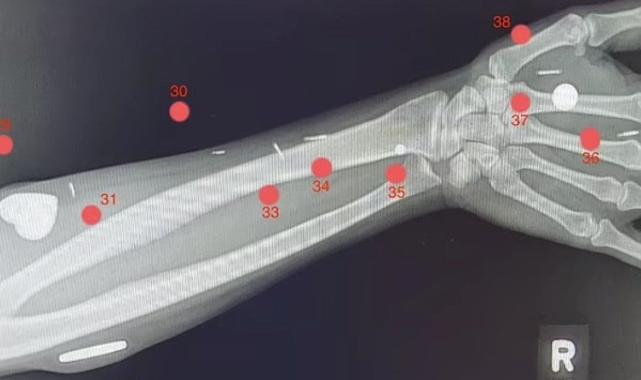

Bu implantlar arasında şimdiye kadar bir insanın içine yerleştirilen en büyük mıknatıs da dahil olmak üzere, kadının vücudunda tam 52 adet çip var.

Synn'in sol elindeki implantlar ona bir nevi altıncı his veriyor. Kadın, mikrodalga fırınların çok fazla radyasyon sızdırıp sızdırmadığını anlayabiliyor ve herhangi bir güç kutusunun yeterli güç alıp almadığını belirleyebiliyor, hatta duvarın arkasındaki akım geçen kabloları bile hissedebiliyor.

Synn, "Sol bileğimdeki kızımın telefonunu, sağ bileğimdeki ise eşimin telefonunu arıyor." diyor.